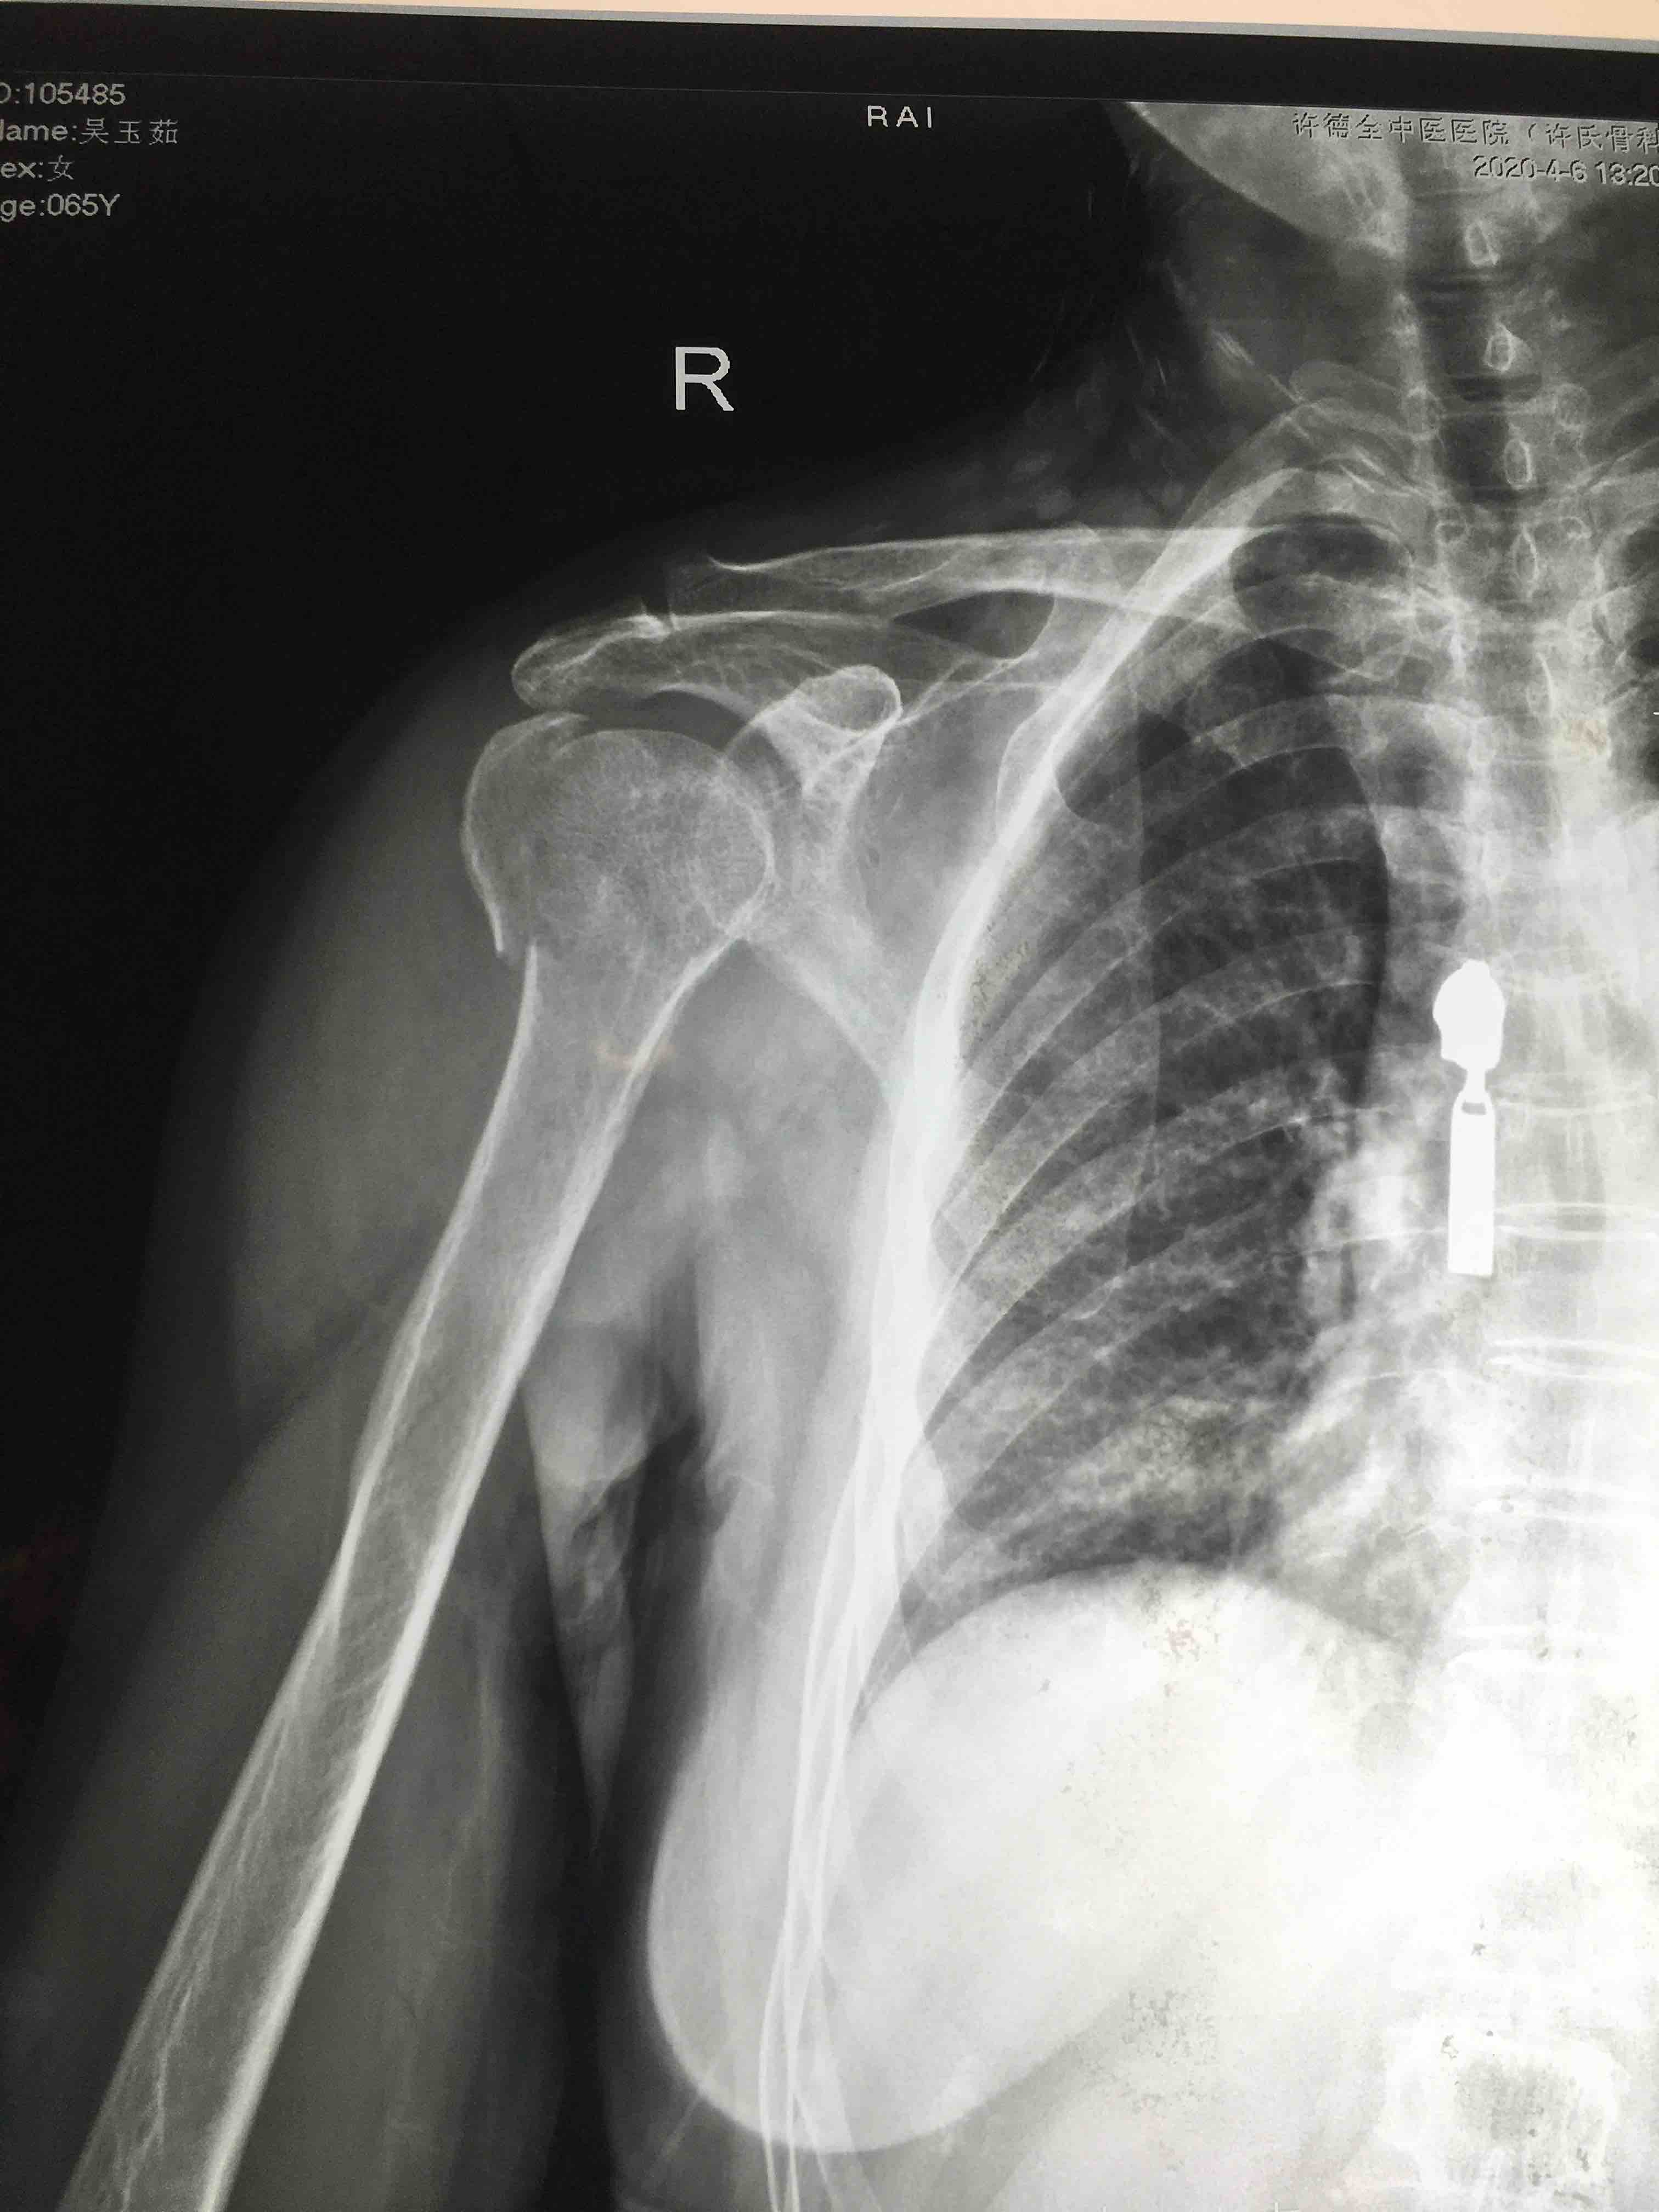

骨折 肱骨外科颈骨折

摔伤后右肩部肿痛,活动受限1小时入院。既往身体一般,无特殊不良嗜好。

生命体征平稳,心肺复未见异常。右肩部肿胀明显,局部皮色发红,皮温高,压痛及纵向叩击痛阳性,肩关节活动受限,末梢血运感觉正常。

诊断右肱骨外科颈粉碎性骨折在臂丛麻醉下行切复内固定术,术后抗炎,消肿等处理。